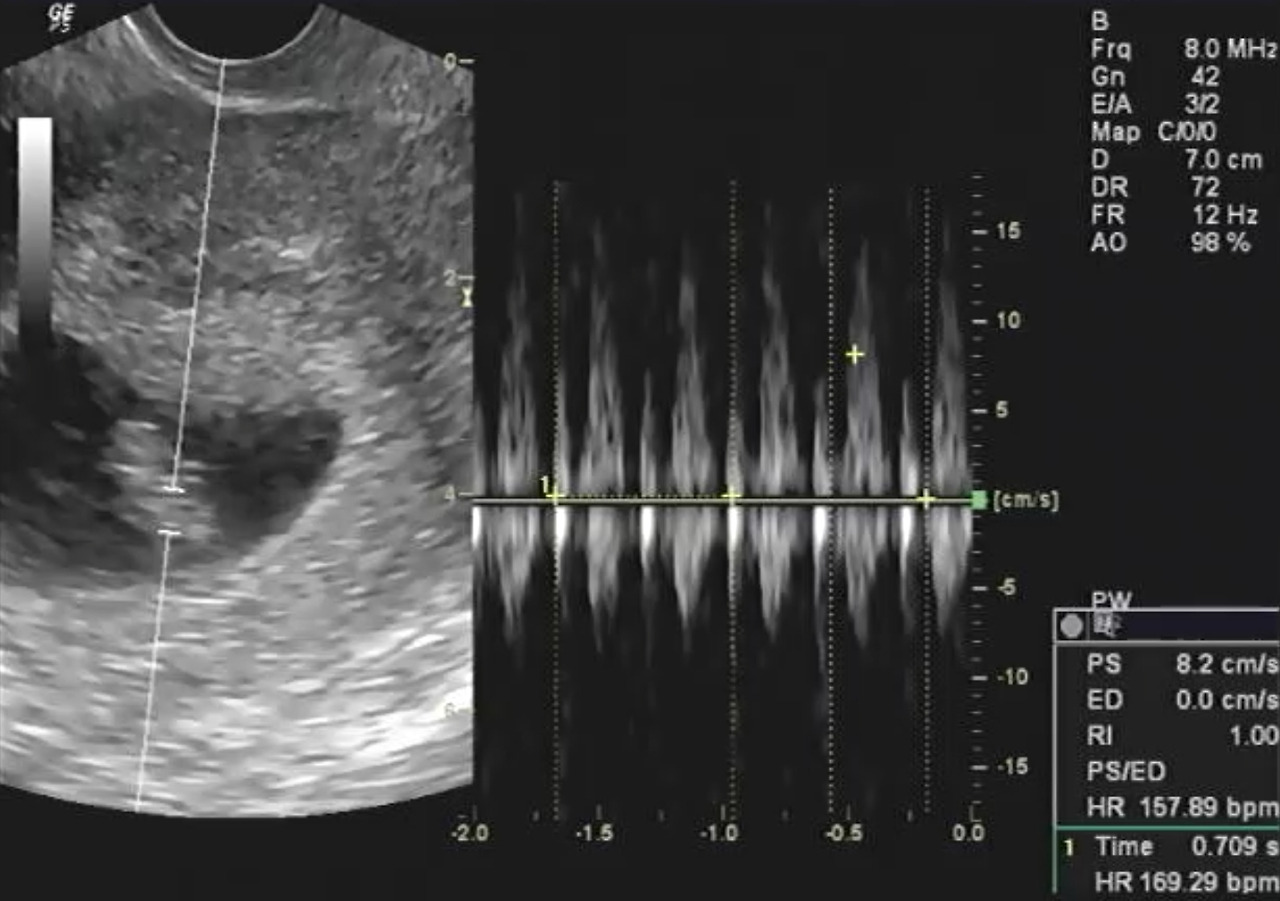

새로운 생명은 힘든 시기를 잘 버텨주었고, 그 누구보다 건강하고 활발한 태아의 모습으로 자라나고 있습니다.

Screenshot_20190114-141624_Video Player.jpg

이제 우리 부부는 하루하루 기대와 기다림 가득한 삶을 살아가고 있어요.